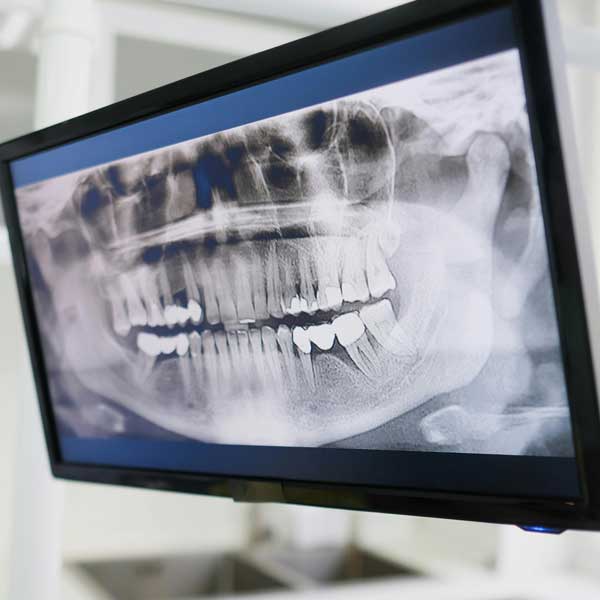

Dexis OP3D CBCT 3D X-Ray System

A standard dental X-ray is flat. The Dexis OP3D gives us a full three-dimensional view of your teeth, jawbone, nerve canals, sinuses, and soft tissue in a single scan taken right here in our Cambridge clinic.

For dental implants, this changes everything. Before Dr. Marwan Elaraby places a single implant, the OP3D has already shown us exactly where your nerves run, the density and volume of your available bone, and the ideal position for each implant. Patients who previously had to travel to imaging centres for a separate CT scan can now have that done on-site, as part of their regular appointment.

The OP3D also supports orthodontic evaluation, TMJ analysis, endodontic planning, airway review, and assessment of impacted teeth. It has built-in dose optimization — the field of view and resolution are adjusted to match what each case actually needs.